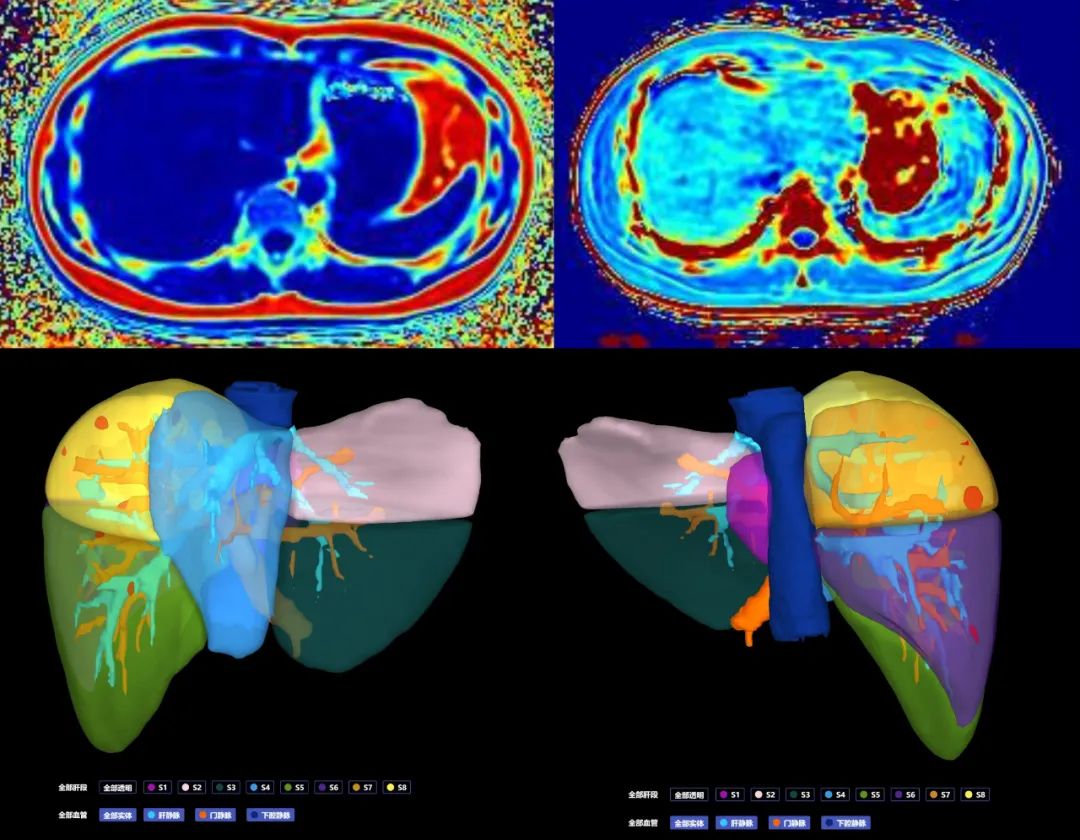

(四)肝臟定量磁共振成像及肝膽特異性對比劑成像普美顯(釓塞酸二鈉)注射液是一種肝細胞特異性對比劑,可以提供普通磁共振增強的圖像,還可以獲得清晰的肝細胞特異性圖像,肝特異性對比劑磁共振增強的優勢在于能發現小于1cm的肝內病灶,為肝癌提供特異性的診斷和鑒別診斷信息,提高肝內病灶的檢出率,有助于肝內病變的準確診斷。

圖片

肝臟定量磁共振成像

肝特異性對比劑MRI增強檢查